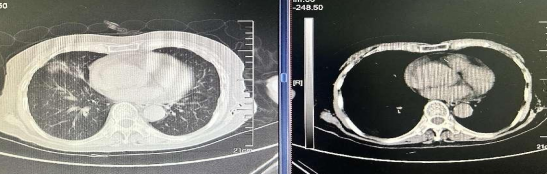

近年来,贵州航天医院各科室紧跟医学前沿,不断强技术、补短板,大力开展新技术、新项目,完成了许多高精尖、高难度、本地区“首例”的技术,填补了医院医疗技术空白,满足了群众日益增长的医疗需求。 贵州航天医院呼吸与危重症医学科是贵州省内呼吸疾病治疗规模最大,诊疗项目最全的呼吸疾病品牌科室,呼吸介入技术达到了全国先进水平,在贵州省内处于领先的地位。 本期,我们将为大家带来呼吸与危重症医学科特色技术——内科胸腔镜技术诊断和治疗胸腔疾病。 案例分享 患者苟某某,因劳累、气促,不明原因胸腔积液在某县一医院采取反复抽水等治疗手段效果不佳,当地医院考虑到患者年龄大(77岁),基础疾病较多,病情复杂,结合当地诊疗水平能力情况,建议转到上一级医院诊治,通过我院与该院建立的呼吸专科联盟绿色通道转入了我院。 患者入院后,呼吸与危重症医学科第一时间复查胸部CT,提示:右肺中叶、左肺感染,纤维化灶,左侧中量胸腔积液,右后侧胸膜轻度增厚,心包少量积液;并完善心电图、血常规、凝血功能、生化指标等术前检查。经科室专家团队集体讨论,得出患者左侧胸腔积液可能原因:结核?恶性?其他?冠心病、心功能不全、高血压病3级(高危组)、陈旧性肺结核复发?肺部感染;为进一步明确诊断,在充分评估、做好术前准备及应急预案、与患者及家属沟通的情况下,决定为患者进行内科胸腔镜检查术。 科室在患者入院第3天便实施了内科胸腔镜检查术,经检查取活检,病理不排除胸膜间皮瘤,送遵义医科大学附属医院病理会诊后诊断:胸膜间皮瘤。明确诊断后,科室专家团队为患者制定了个体化的治疗方案,患者病情很快得到有效控制,最终满意出院。半年后,医院通过电话回访,患者病情稳定,生活质量明显改善。 什么是内科胸腔镜 内科胸腔镜(medical thoracoscopy,MT)是一项微创诊断和治疗胸腔疾病的重要技术。主要应用于无创方法不能确诊的胸腔积液和胸膜疾病,通过局部麻醉后在胸壁做一个小切口,插入胸腔镜,直接观察胸膜、肺表面、纵隔等部位的病变情况,可进行活检、粘连松解及胸膜固定等操作。具有创伤小、恢复快、诊断准确性高等优点。 内科胸腔镜原理 内科胸腔镜是一项利用现代光学技术和成像技术的侵入性操作技术,应用电子支气管镜、硬质或软硬结合(半硬)的胸腔镜的一种电子内窥镜,末端装有连接着显示屏的微型摄像头。通过胸壁1-2cm左右的小切口,将内科胸腔镜及专用器械(戳卡套管)通过小切口进入胸腔,微型摄像头将胸腔内的情况投射到显示屏幕上,医生可以通过镜头全面、直观地观察患者胸腔内情况,了解胸膜病变确切位置和形态改变,还可对胸膜上的病变进行活检及治疗的操作技术,安全、微创、几乎无痛地“揭秘”不明原因的胸腔积液。 内科胸腔镜技术优势 (一)安全性高:仅需局部浸润麻醉,并发症发生率相对较低,对患者的身体条件要求较低。 (二)操作简便:操作时间短,痛苦少,患者耐受好。 (三)微创性:切口小,对患者身体损伤小,术后疼痛轻,恢复快。 (四)高分辨率成像:清晰显示胸腔内细微病变,提高诊断准确性。 (五)可直视操作:直接观察病变,进行精准活检和治疗。 (六)适用范围广:可用于不明原因胸腔积液、胸膜疾病、肺部疾病等的诊断和治疗。 (七)费用低:与外科胸腔镜比较费用低廉。 内科胸腔镜技术是贵州航天医院呼吸专科和呼吸介入诊疗优势的一部分,在2016年率先开展了内科胸腔镜技术,年手术量约100余例,已建立了快速、精准、规范、有效的一体化诊疗服务体系。目前呼吸与危重症医学科内科胸腔镜技术广泛应用于不明原因胸腔积液、气胸、脓胸的诊断和肺癌、弥漫性恶性胸膜间皮瘤等的分期,恶性或复发性胸腔积液、早期脓胸、自发性顽固性气胸的治疗。 镜下常见表现:单发或多发结节、灰白色弥漫性粟粒样结节、胸膜充血、水肿、胸膜增厚及纤维分隔或粘连带形成。 诊断方面: 胸腔积液的病因诊断。内科胸腔镜对恶性胸腔积液的诊断率可高达90%以上,胸腔镜对结核性病变诊断率极高,几乎达到96%以上。 腺 癌 恶性淋巴瘤 软骨肉瘤胸膜转移 滑膜肉瘤胸膜转移 结核性胸膜炎 治疗方面: 脓胸 肺大泡 贵州航天医院 呼吸与危重症医学科学科带头人 廖江荣 国务院政府特殊津贴专家 二级教授 主任医师 贵州航天医院副院长 国家级学术任职: 第二届中国医药教育协会介入微创专业委员会呼吸分会副主任委员 中国抗癌协会肿瘤微创治疗专业委员会常务委员 中国防痨协会结核病转化医学专业分会常务委员 第一届中国人体健康科技促进会呼吸介入专委会常务委员 中国医疗保健国际交流促进会结核病学分会第三届委员会常务委员 中国抗癌协会肿瘤微创治疗专业委员会粒子治疗学组第四届委员会委员 中华医学会结核临床专业委员会内镜介入委员 中华医学会放射学分会第十五届委员会介入学组呼吸系统介入专业委员会委员 北京健康促进会中青年专家委员会胸部疾病精准活检分委会副主任委员 中国医师协会介入医师分会第二届委员会肿瘤消融专业委员会委员 中国结核病防治综合质量控制专家指导委员会委员 亚洲冷冻治疗学会常务委员 世界内镜医师协会呼吸内镜协会常务理事 内镜临床诊疗质量评价专家委员会委员 “西部呼吸介入联盟”副理事长 专业擅长: 贵州航天医院 呼吸与危重症医学科简介 贵州航天医院呼吸与危重症医学科以呼吸危重症和介入呼吸病学为强力推手,以肺部感染性疾病及肺癌、肺小结节的早期精准诊疗、慢性呼吸疾病康复治疗为特色,以人才团队建设为核心的科室发展模式,现已成为省内呼吸疾病治疗规模最大,诊疗项目最全的呼吸疾病品牌科室。是贵州省医学重点学科、临床医学重点专科建设单位,遵义市首批呼吸重点学科、重点专科建设单位。是国家卫健委能力建设和继续教育肿瘤微创介入建设中心、贵州省县级医院微创介入培训中心、遵义市呼吸疾病临床医学中心。是国家呼吸医疗质量控制与管理哨点医院、遵义市呼吸内科专业医疗质量控制中心。是中国医药教育协会介入微创呼吸分会呼吸介入技术培训中心单位;国家卫健委海医会呼吸分会ROSE专委会“诊断性介入肺脏病学快速现场评价”培训基地;中国肺癌防治联盟“贵州航天医院肺结节诊治”分中心,中国人体健康科技促进会呼吸介入技术培训基地,贵州省中西医结合会呼吸学分会呼吸介入专委会主委单位。 基本情况 平均每年开展气管镜诊疗约4000例,经皮肺穿刺介入诊疗近千例,开展的项目包括经支气管镜(软、硬)下冷冻、氩气刀、高频电刀、球囊扩张、支架置入、超声内镜诊疗等气道介入诊疗技术,经皮肺穿刺活检及肿瘤消融术(微波、冷冻)、ROSE技术、内科胸腔镜诊疗及经血管介入诊疗技术,且多项呼吸介入诊疗技术在省内处于领先水平。 诊疗范围 航天医院呼吸专科擅长:致力于呼吸系统感染性、疑难性疾病的介入快速精准诊疗;肺癌与肺小结节早期精准诊疗水平项目提升。擅长于呼吸系统(肺)疑难病的诊断及危重病的救治,尤其在肺癌、肺小结节的早期诊断;肺癌综合靶向治疗;肺结核综合诊疗;肺部疾病的介入诊疗在省内处于前沿水平。 咨询热线 (一)呼吸与危重症医学科一病区 医生办公室:27677317 护士站:28614217 (二)呼吸与危重症医学科二病区 医生办公室:28691274 护士站:28690442 (三)呼吸与危重症医学科三病区 医生办公室:28692417 护士站:28690461 (四)呼吸与危重症医学科四病区 医生办公室:28616402、27677582 护士站:28614987、27677862